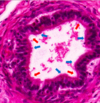

הסלייד הבא נלקח ממערכת הרביה הזכרית, מה רואים בו?

מה מסומן בחץ מספר 2?

Seminiferous tubules

Spermatid

הסלייד הבא נלקח ממערכת הרביה הזכרית, מה רואים בו?

מה מסומן בחץ מספר 1?

Seminiferous tubules

Spermatogonium

הסלייד הבא נלקח ממערכת הרביה הזכרית, מה רואים בו?

מה מסומן בחץ מספר 3?

Seminiferous tubules

Primary Spermatocyte